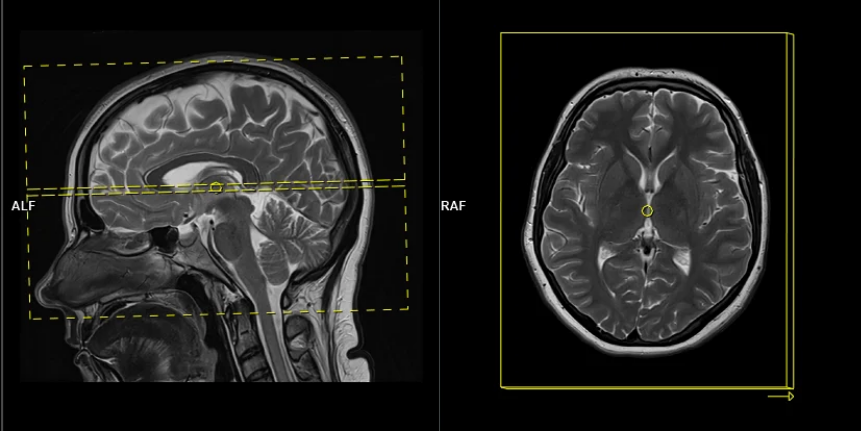

So far we used a gradient along z to select a thin slice in the z-direction (1D pattern). Can we excite an arbitrary 2D pattern? Yes.

By playing time‑varying gradients in two orthogonal directions (x and y) while transmitting a shaped RF waveform, the RF tips spins at specific x–y locations. A simple picture: the gradients change which position is “in tune” with the RF, and the RF turns spins on at those positions — like steering a paintbrush while painting.

Under the common “small‑tip‑angle” approximation, the excited transverse magnetization pattern is (approximately) the 2D Fourier transform of the RF waveform sampled along the path the gradients trace through “excitation k‑space.” Excitation k‑space is the 2D Fourier domain: each k‑space coordinate corresponds to a spatial frequency. By choosing the k‑space trajectory (for example, spiral) and designing the RF accordingly, you can synthesize many useful 2D patterns; the trajectory’s extent and sampling density set the achievable field‑of‑view and resolution.

A “pencil‑beam” excitation creates a narrow, cylindrical region of magnetization. By positioning this small beam over the liver you get a continuous signal that changes as the patient breathes: the liver moves with respiration, and that motion modifies the measured signal. This motion signal is used as a respiratory trace to accept data only during a chosen breathing phase (for example, end‑expiration) and to reject data acquired at other times, reducing motion artifacts in cardiac MRI.